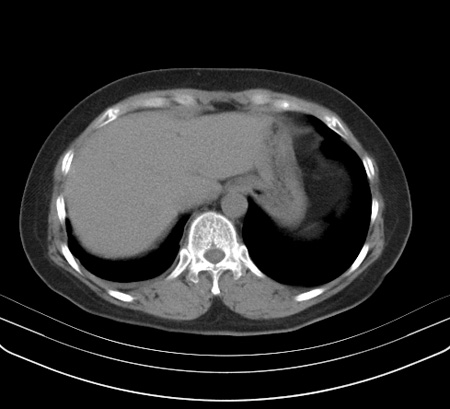

以下是引用余辉在2009-2-19 20:10:00的发言:[br]多考虑急性感染性病变,右中叶尚可见多枚小斑片状影,多为化脓性肺炎,双侧胸腔积液

以下是引用随光逐影在2009-2-19 20:33:00的发言:[br]1)考虑右肺炎症;建议抗炎治疗后复查。2)双侧胸腔积液(以右侧为甚)。

以下是引用花凤凰在2009-2-19 20:46:00的发言:[br]病人有发热,胸痛急性起病,主要病变位于右肺中叶外侧段,呈楔行改变,位于外带胸膜下,考虑为肺梗塞可能!!!!!!!!!!!!!!!!!!!!!!!!!!!!!!!!!!!